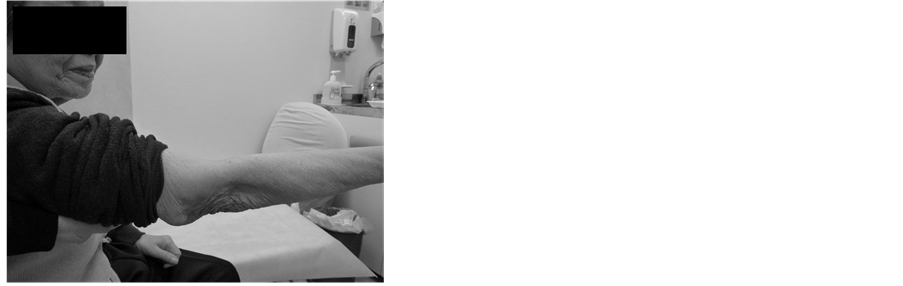

After teriparatide treatment for the 12 months, the range of motion at the elbow joint was good (range: −10 - 130), and she had no problems with activities of daily living (Figure 4).

Figure 4. After teriparatide treatment for the 12 months. The range of motion ((a) extension; (b) flexion) is good.